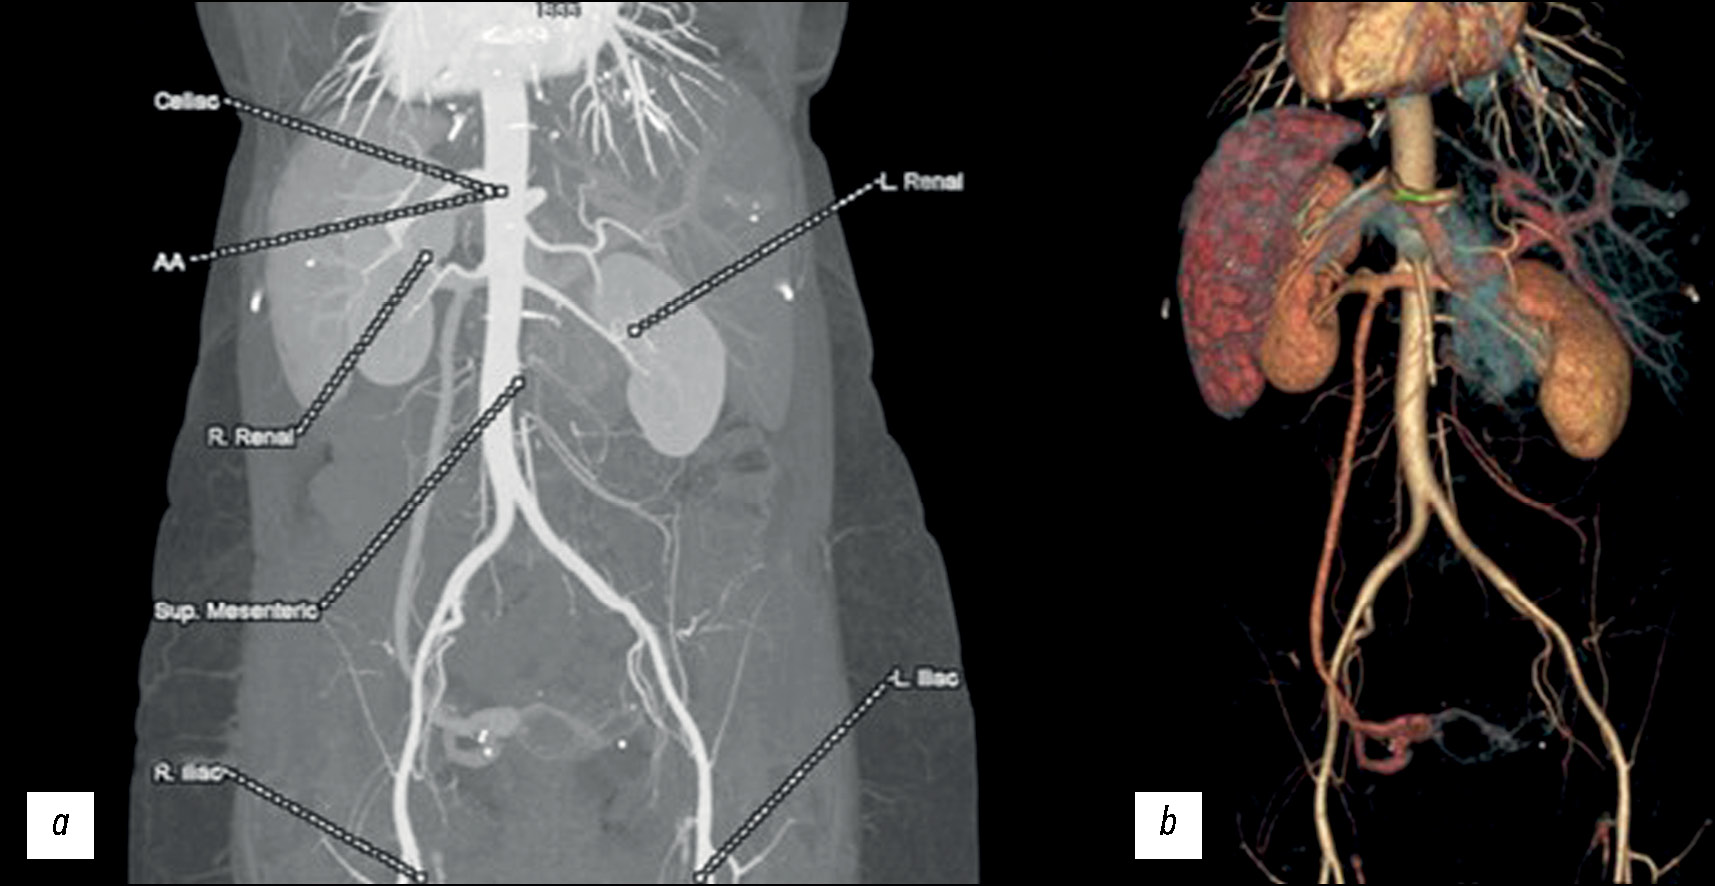

This condition could affect the chest, particularly the heart and large blood vessels because each cardiac chamber is asymmetrical; situs also applies to the heart. In addition, the anatomy of the arteries and the abdomen is mirrored (Fig. 7).

Fig. 7. The artery’s anatomy of the abdomen in the case of SIT: on the left, there is the liver, and the spleen is on the opposite side. The first is an angio-map (a) while the second is a VR image (b).